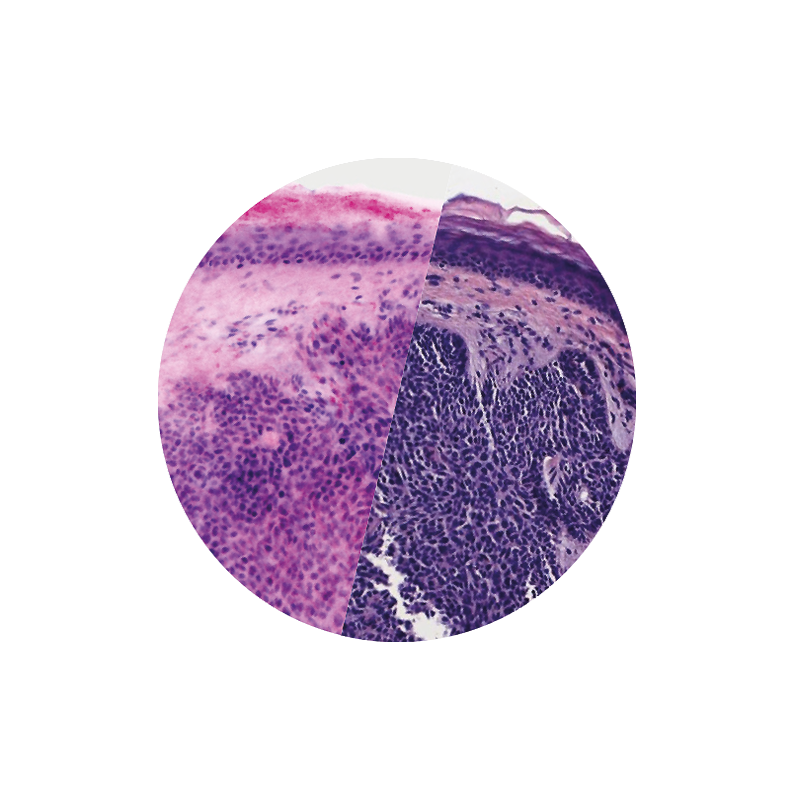

VivaScope Ex Vivo technology allows for direct pathological assesment during surgery. Like H&E staining, VivaScope images are generated from two components. Two lasers of different wavelengths create two distinct images, a fluorescence image and a reflectance image. Both signals are scanned simultaneously and are used to create pseudo-colored images. The device’s software uses an algorithm to translate the acquired image information into colors that resemble H&E.

Images courtesy of Dr Javiera Pérez-Anker. Basal cell carcinoma; imaged with the VivaScope 2500 (left) and after H&E staining (right).